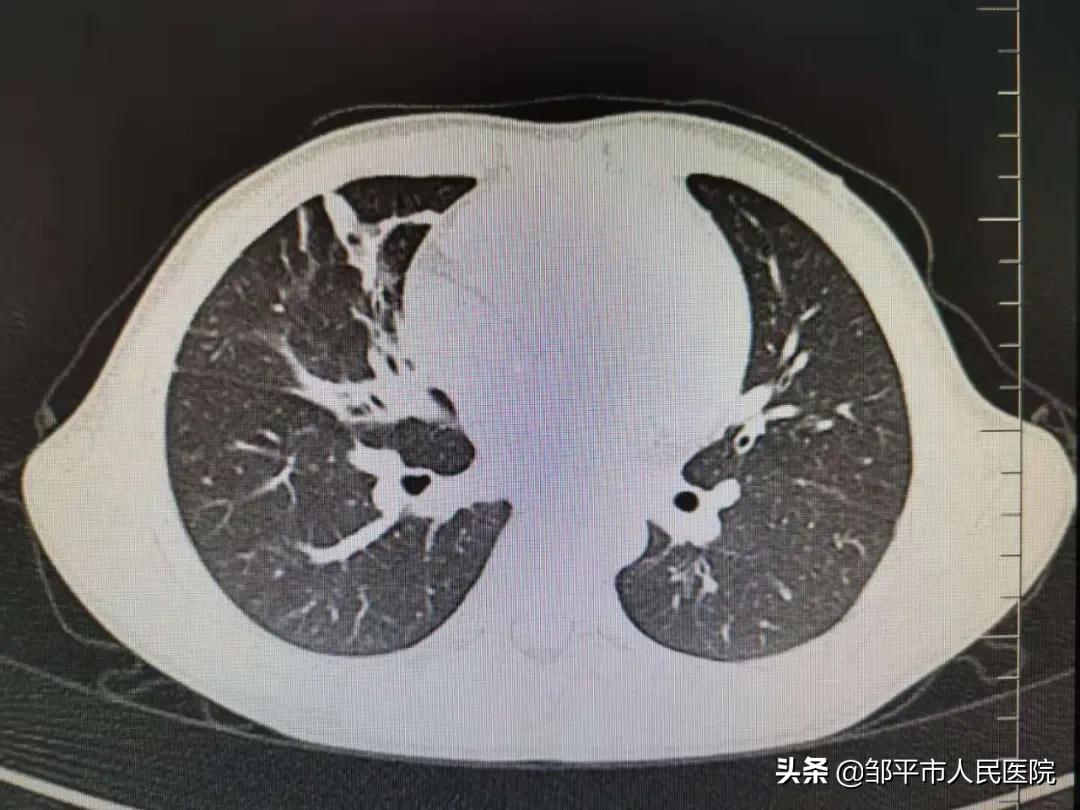

清洗后

两名患儿的体温很快降至正常,咳嗽咳痰消失,复查胸部CT肺脏完美复张,孩子们均康复出院。